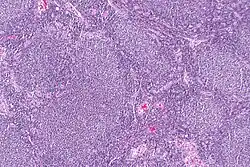

| Micrograph of a follicular lymphoma, showing the characteristically abnormal lymphoid follicles that gave the condition its name. H&E stain. | |

Follicular lymphoma (FL) is a cancer that involves certain types of white blood cells known as lymphocytes. This cancer is a form of Non-Hodgkin Lymphoma and it originates from the uncontrolled division of specific types of B-cells (centrocytes and centroblasts). These cells normally occupy the follicles (nodular swirls of various types of lymphocytes) in the germinal centers of lymphoid tissues such as lymph nodes. The cancerous cells in FL typically form follicular or follicle-like structures (see adjacent Figure) in the tissues they invade. These structures are usually the dominant histological feature of this cancer.[1]

The diagnosis of FL depends on examining involved tissues for histological, immunological, and chromosomal abnormalities that are indicative of the disease. FL usually involves enlarged lymph nodes populated by abnormal follicles (see adjacent picture) that when examined histologically contain a mixture of centrocytes or centroblast surrounded by non-malignant cells, mostly T-cells. The centrocytes, which typically outnumber centroblasts, are small to medium-sized B-cell lymphocytes that characteristically exhibit cleaved nuclei; the centropblasts are larger B-cell lymphocytes without cleaved nuclei.[9] Rare cases of FL may show lesions that contain tissue infiltrations dominated by B-cells with features of precursor (i.e. "blast") cells, monocytes, or malignant mantle cells such as those found in mantle cell lymphoma.[1] Immunochemical analyses reveal that these cells generally express B-cell surface markers including the CD10 (60% of cases), CD20, CD19, CD22, and CD79 but not CD5, CD11c, or CD23 cell surface proteins;[2] genomic analyses reveal that these cells contain t(14:18)(q32:q21.3) translocation (85–90% of cases), 1p36 deletions (60–70% of cases), and with far less frequency the other genomic abnormalities listed in the above sections on Pathophysiology and Presentation and course. None of these protein markers or genomic abnormalities are diagnostic for FL, e.g. the t(14:18)(q32:q21.3) translocation is found in 30% of diffuse large B-cell lymphoma and in a small number of reactive benign lymph nodes. Rather, the diagnosis is made by a combination of histological, immunological, and genomic abnormalities.[2] According to World Health Organization (WHO) criteria, follicular lymphoma can be classified morphologically by the relative amount of centroblasts. However, such classification is optional, due to poor reproducibility and little difference in prognosis and treatment, except that a lymphoma with almost only centroblasts may be diagnosed as a diffuse large B-cell lymphoma (DLBCL).[48] The optional classification of follicular lymphoma is as follows:[49]